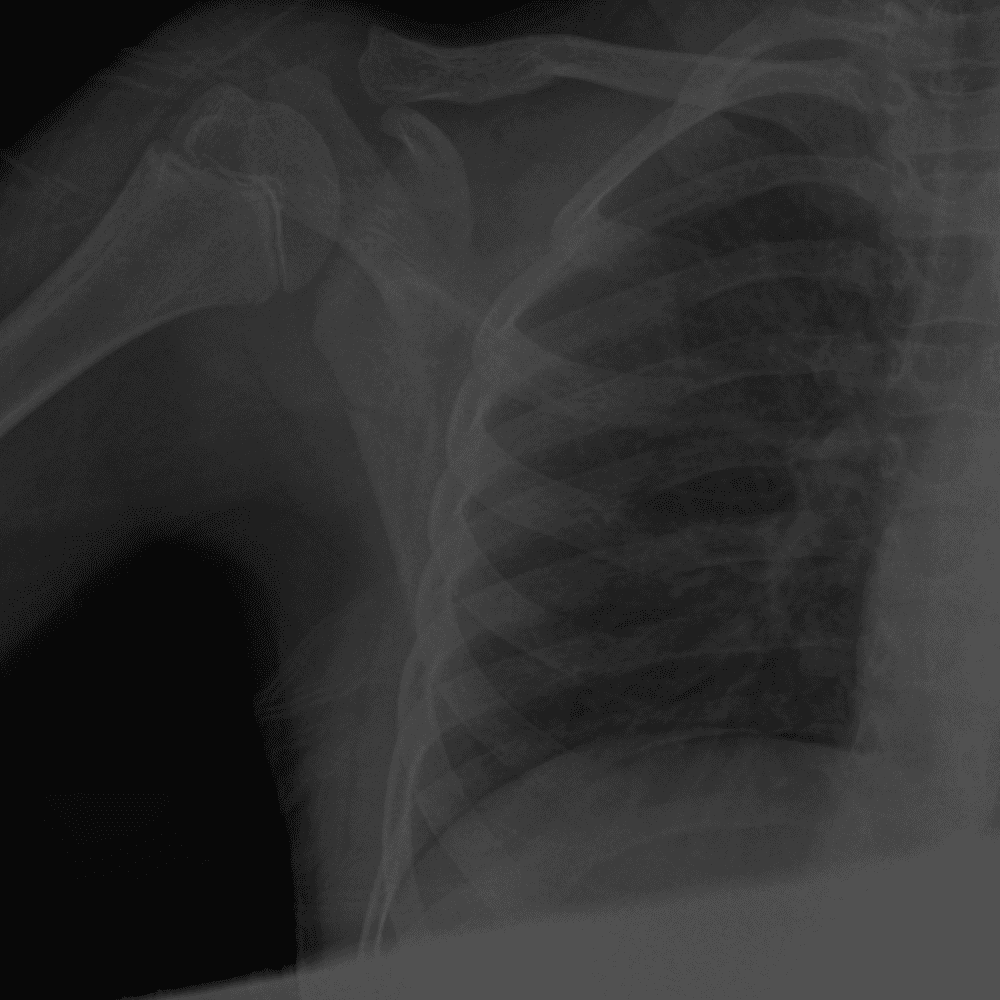

Simuliert den Dienst durch subtile oder schwierige Fälle und einige Normalbefunde.

30 Fälle